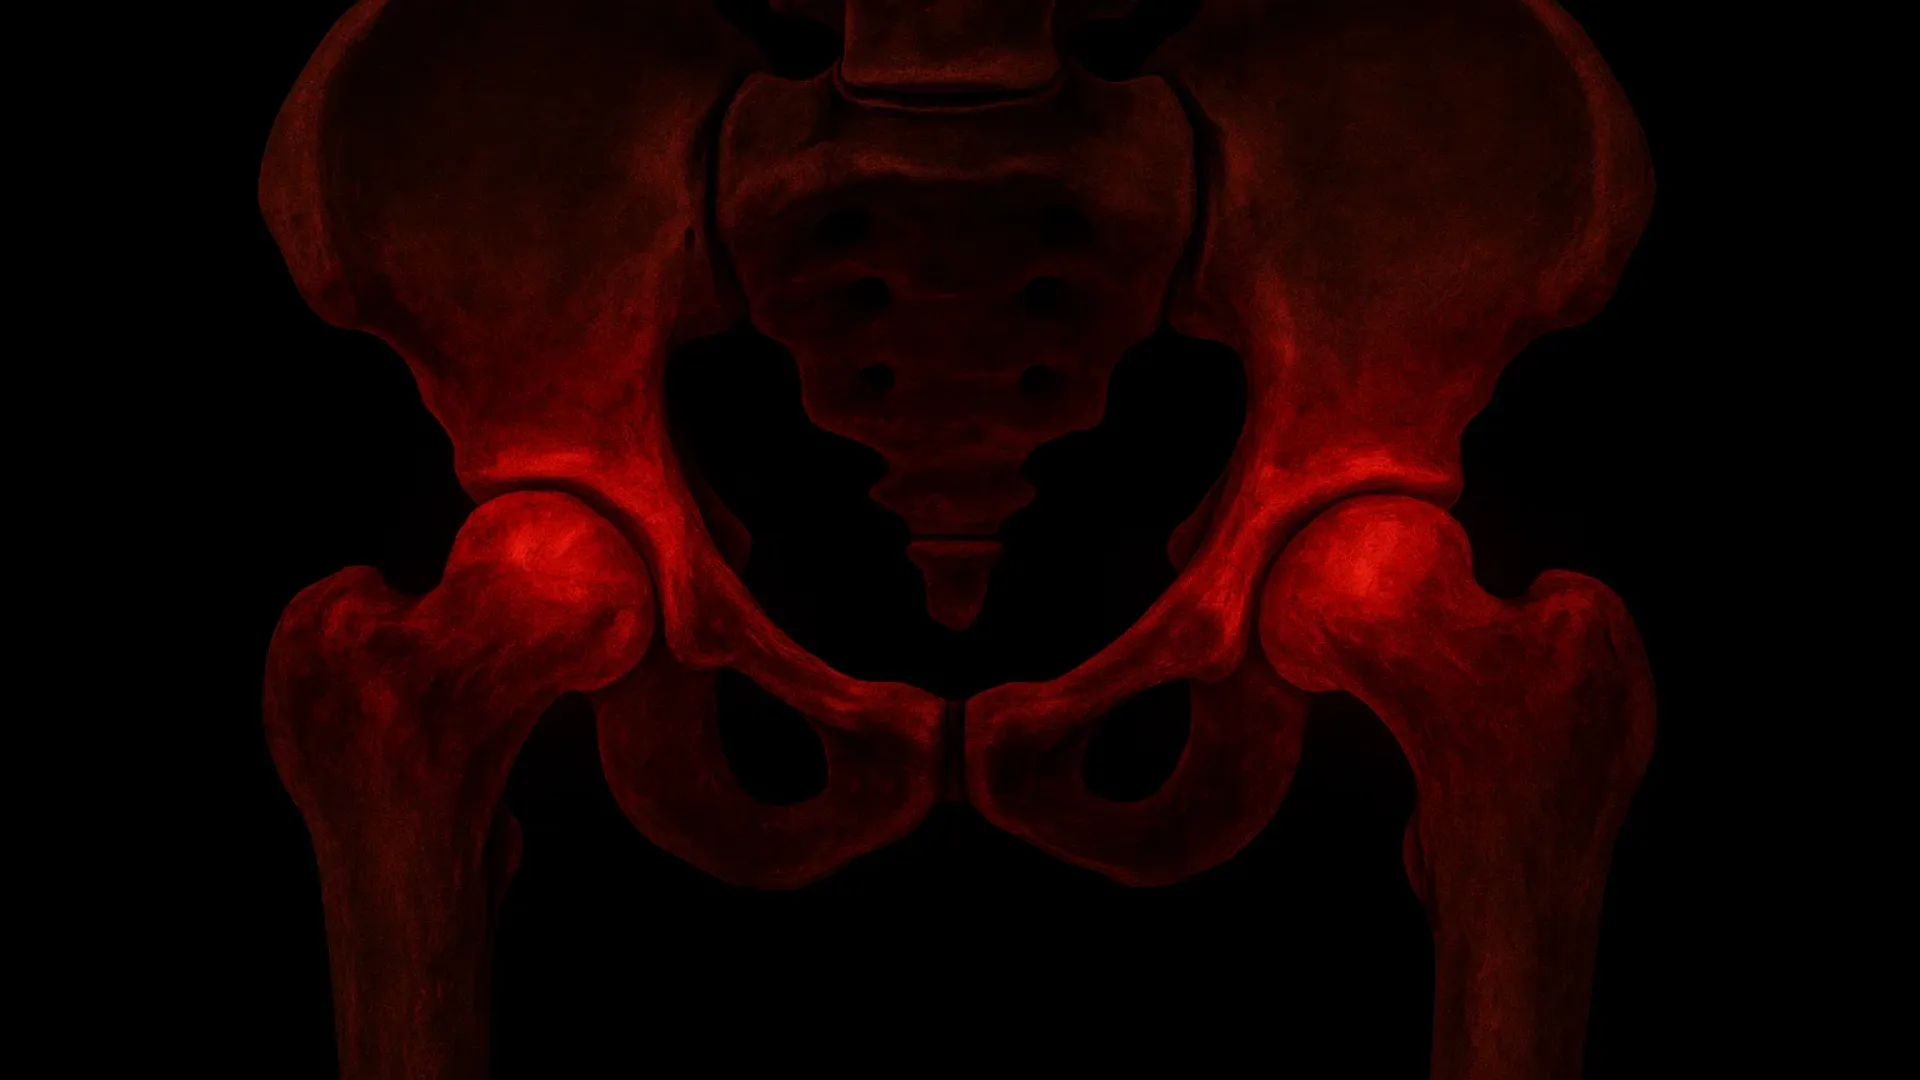

Наиболее грозным ранним осложнением вывиха бедра является повреждение седалищного нерва (обычно происходит при задних вывихах), приводящее к стойкому онемению, слабости и болям в ноге, или повреждение крупных сосудов, угрожающее кровопотерей и некрозом головки бедра.

Поздние осложнения включают посттравматический коксартроз (артроз тазобедренного сустава), а также остеонекроз головки бедренной кости, во время которого происходит отмирание костной ткани из-за прекращения кровотока. При недостаточной реабилитации или нестабильности сустава могут возникать повторные (привычные) вывихи.